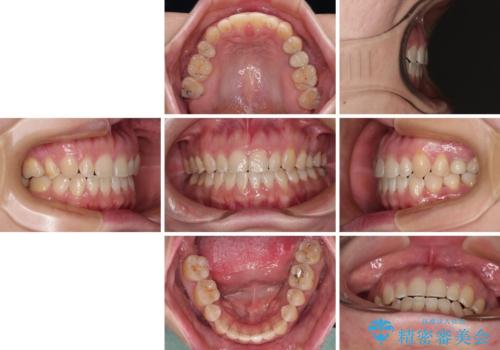

隙間の空いた歯列とボロボロの乳歯 インプラント治療と矯正治療

- 隙間の多い歯列や傾斜した奥歯、むし歯の酷い残存乳歯を気にして来院された患者様です。

歯列はワイヤー矯正にて改善することとしましたが、上下歯列にも隙間があったので、舌の突出癖を改善するトレーニングを徹底的に行うこととしました。

傾斜した下顎の奥歯は、矯正治療にてまずは歯軸を改善させ、隙間が閉じられるようであればそのままに、閉じられないようであればインプラント治療を行うこととしました。

上顎のむし歯の酷い残存乳歯は抜歯をし、矯正治療の途中でインプラントを埋入、矯正治療後に補綴治療を行うこととしました。

舌の突出癖改善のトレーニングが全くうまくできず、治療期間が長期化しました。

早く治療を終えたいとの要望があり、トレーニング次第と伝えるとようやく練習をするようになり、その後は速やかに上下の隙間が改善されました。